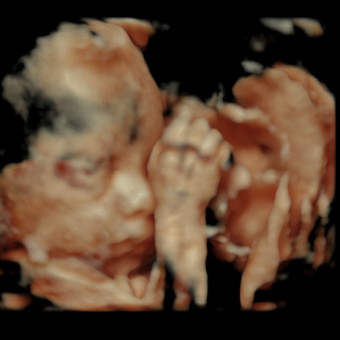

Hi friends! Maximilian Gabriel David is due to arrive March 12, 2026!